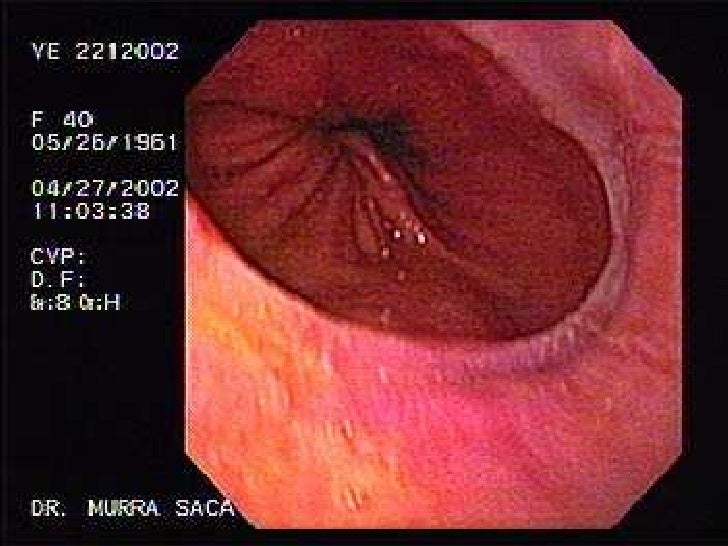

Esófago, hernia hiatal, y acalasia

Optativa DDI 2014: Caso discutido em 26/03 - Rx Contrastado